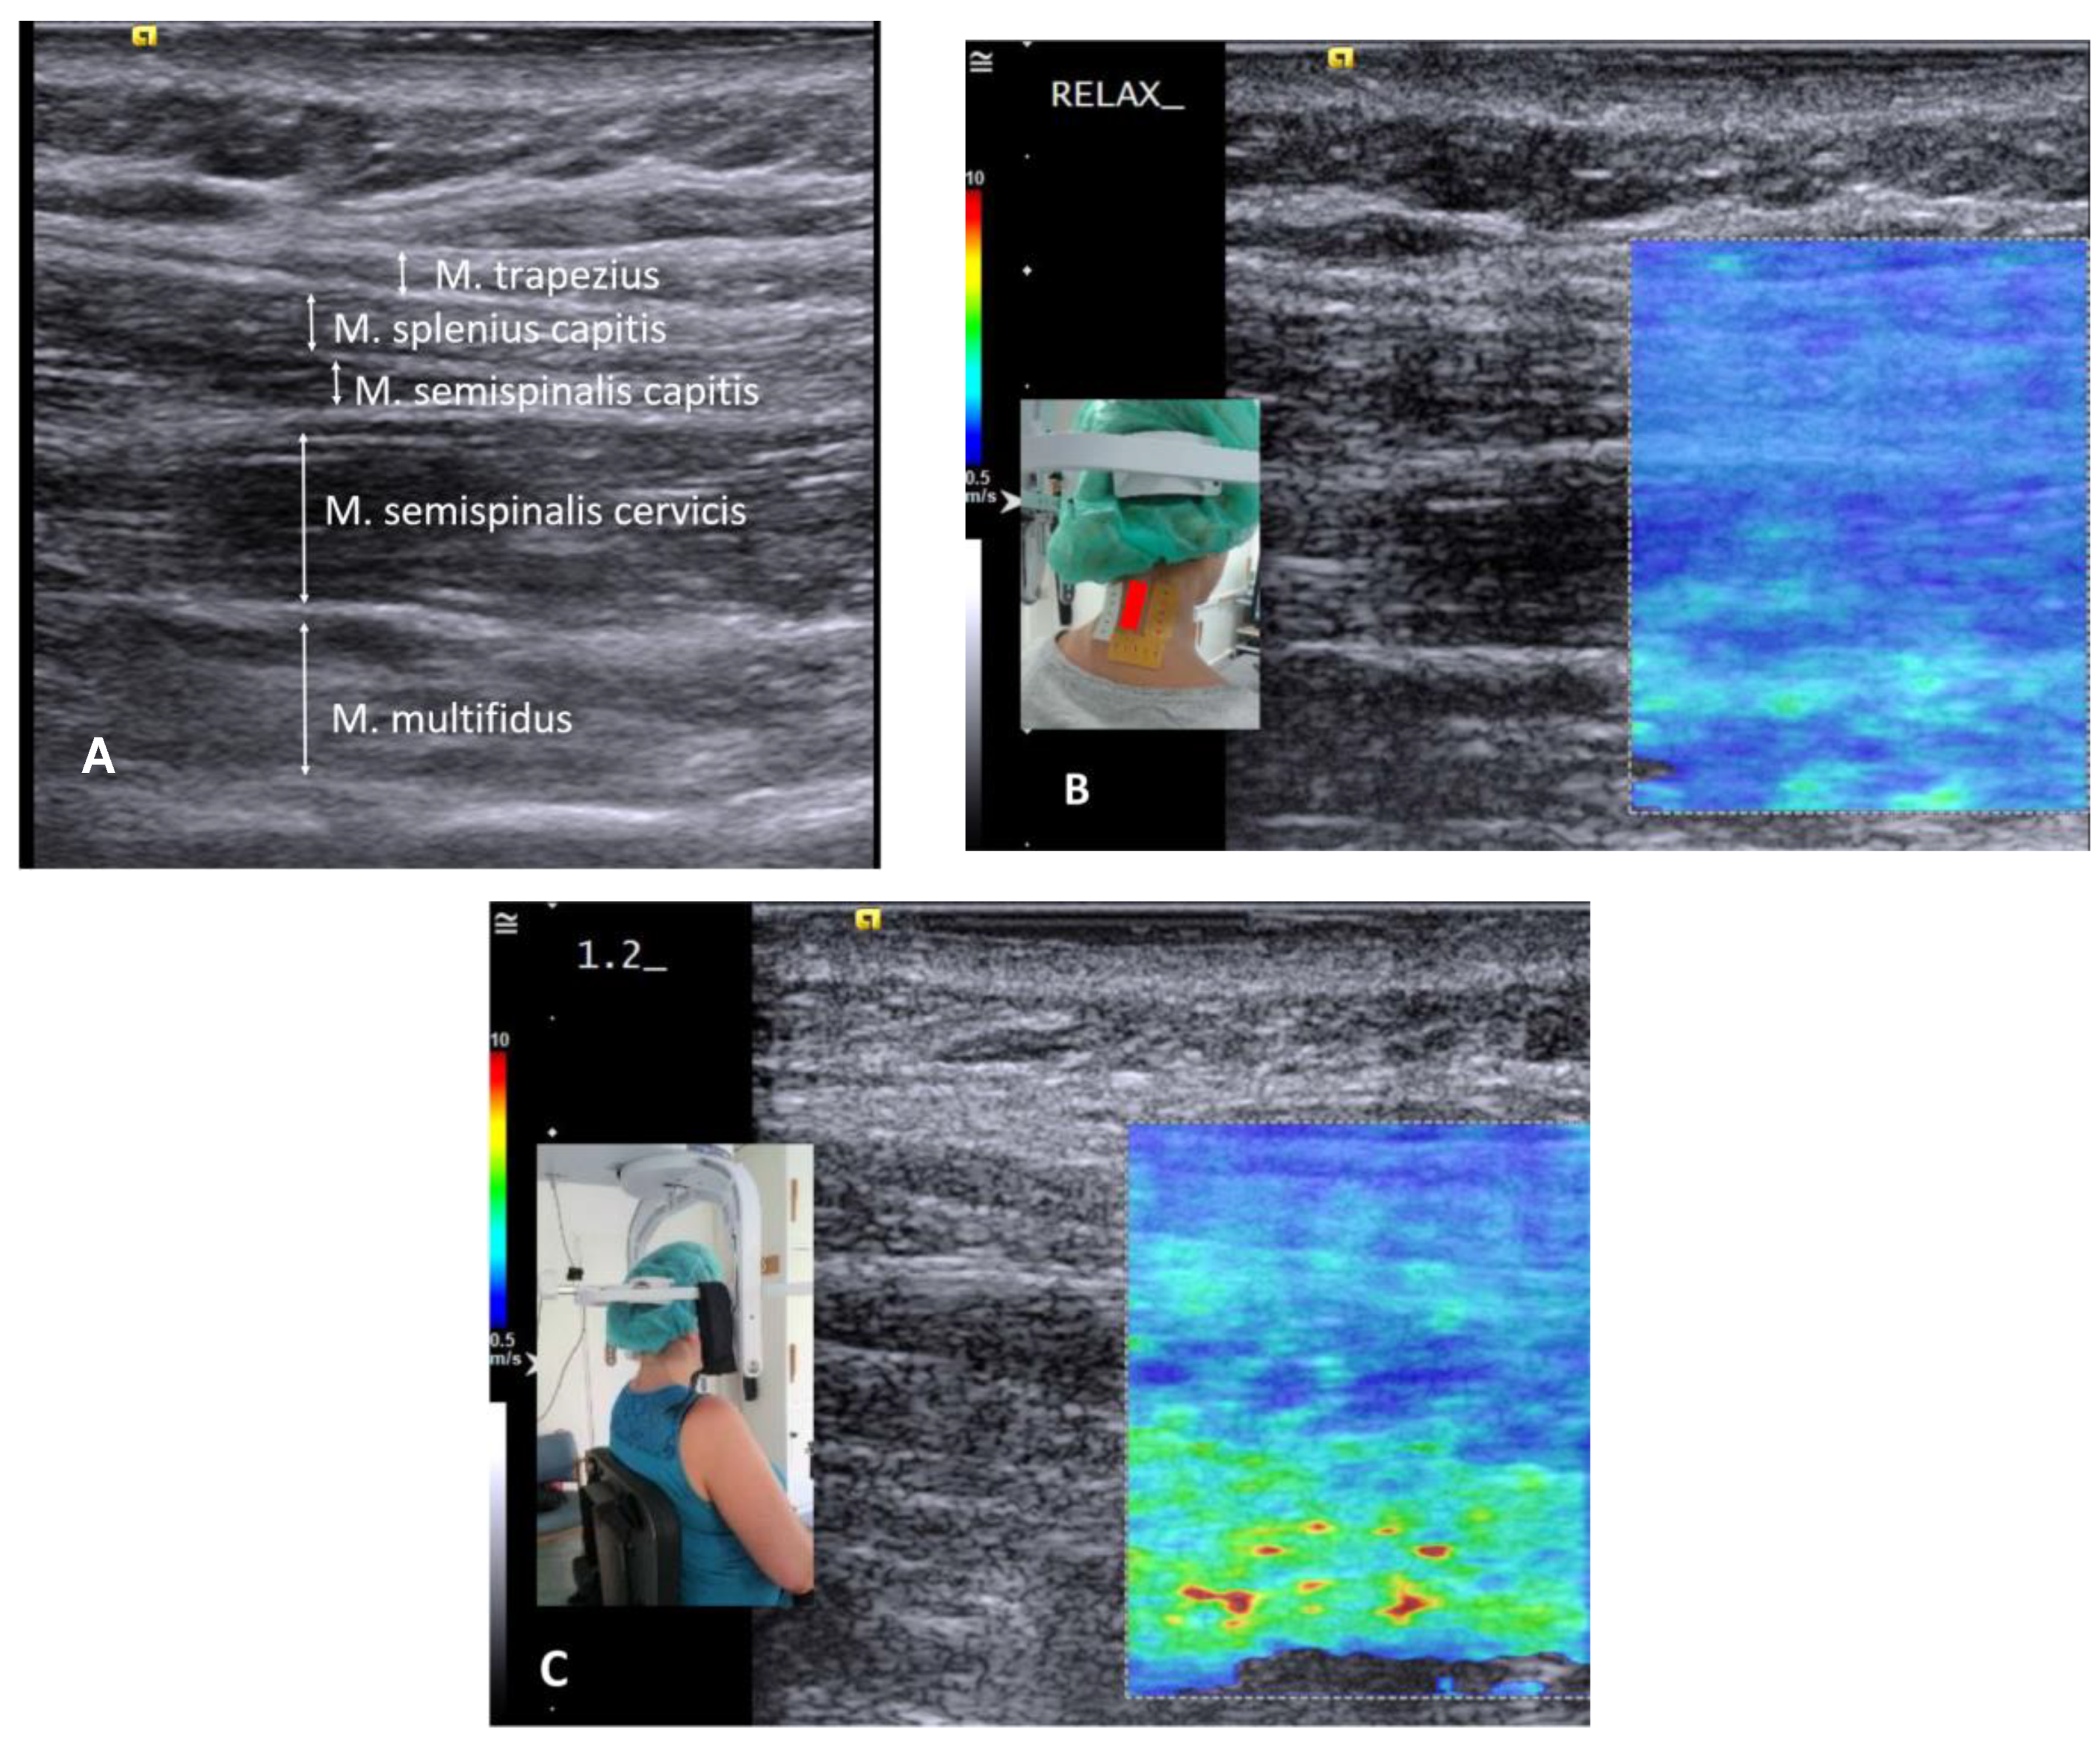

:1. Introduction

2. Materials and Methods